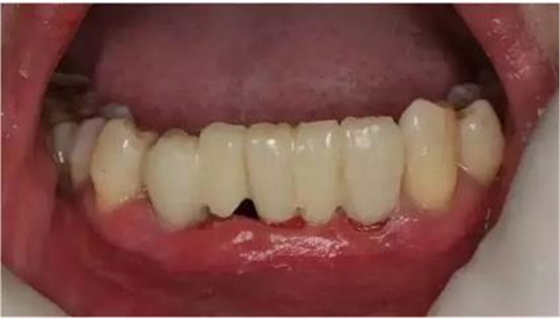

初診時(shí)下前牙不良修復(fù)體

去除不良修復(fù)體后鄰牙松動(dòng)